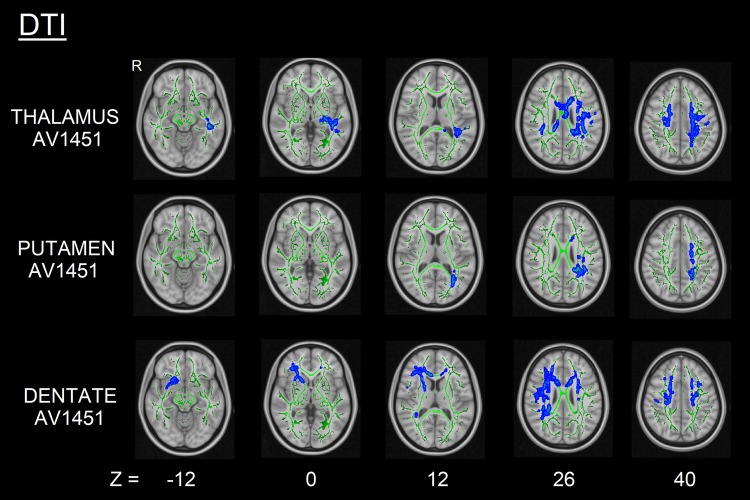

Fig. 4.

DTI changes (increased RD, blue) correlated with thalamic, putaminal, and dentate 18F-AV1451 BPND in PSP subjects (FWE-corrected p < 0.05)

Higher thalamic, putaminal, and cerebellar dentate 18F-AV1451 BPND were correlated with lower GM volume (all uncorrected p < 0.001, k = 20 voxels) (Fig. 2), more pronounced cortical thinning (all uncorrected p < 0.001, k = 36 vertices) (Fig. 3) and altered white matter metrics (e.g., increased MD/RD or decreased FA) (FWE-corrected p < 0.05) (Fig. 4). More specifically, higher thalamic 18F-AV1451 BPND was associated with GM volume reduction in bilateral SMA, precentral gyrus, and right cerebellum; decreased CTh in right latero-occipital, fusiform, and inferior parietal gyri; and DTI alterations in bilateral internal capsule, corona radiata, posterior thalamic radiations, SLF, body of corpus callosum, cingulate white matter, and superior fronto-occipital fasciculus.

Higher putaminal 18F-AV1451 BPND was correlated with lower GM volume in bilateral precentral gyrus, left SMA and parahippocampal gyrus, as well as right superior and middle frontal gyri; reduced CTh in the right precuneus and DTI alterations in bilateral internal capsule, corona radiata, cingulate white matter, and SLF.

Finally, higher 18F-AV1451 BPND in the cerebellar dentate gyrus was correlated with GM volume loss in bilateral cerebellum and precentral gyrus, right superior and middle frontal gyri, and left thalamus; CTh reduction in left superior and middle frontal gyri; and DTI alterations in genu and body of corpus callosum, bilateral corona radiata, SLF and superior fronto-occipital fasciculus, right internal capsule, posterior thalamic radiations, and cingulate white matter.